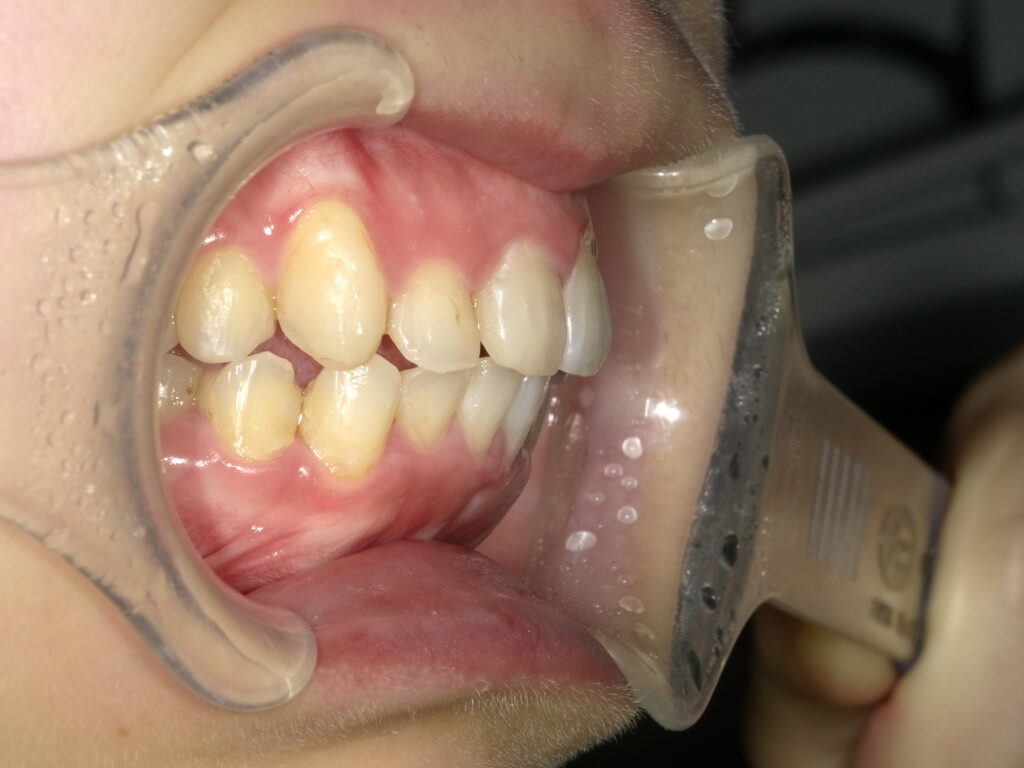

オーバージェット

治療前

治療後